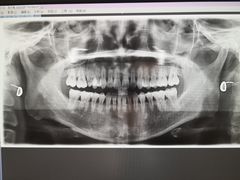

• TSK齿科德申会口腔门诊·联洋诊所

• -TSK齿科德申会口腔门诊·联洋诊所

mochenchen1986 | 20-08-12